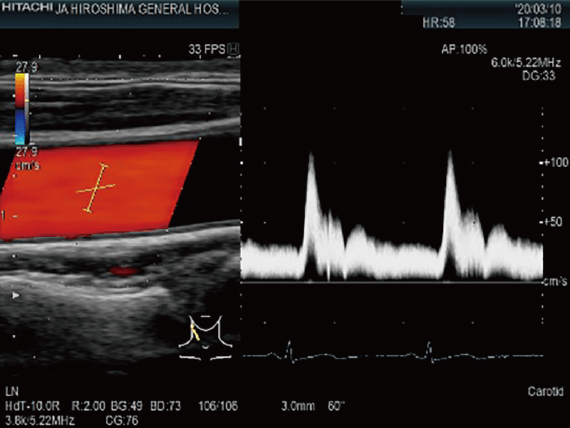

頸動脈超音波検査

胸頸部より超音波を照射し,頸動脈を観察する検査です。動脈硬化やプラークによる血管狭窄・閉塞などの評価に用いられます。